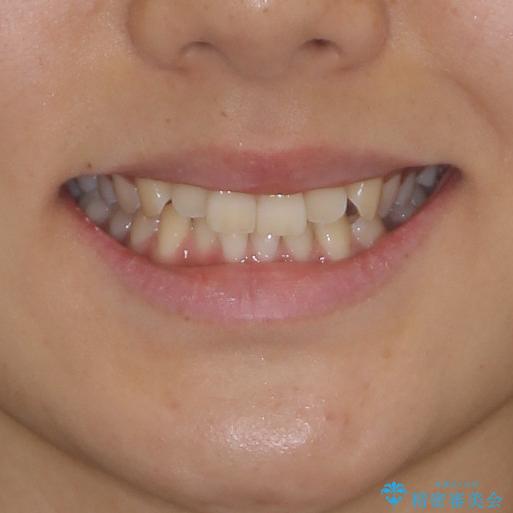

- 前歯の叢生と、奥歯の咬み合わせの悪さを気にして来院された患者様です。

左下には後続永久歯の欠損した乳歯が残存しており、叢生を相まって咬合関係が乱れていました。

乳歯は抜歯し、インビザラインにて矯正治療を行いながら、並行してインプラントによる補綴治療を行うこととしました。